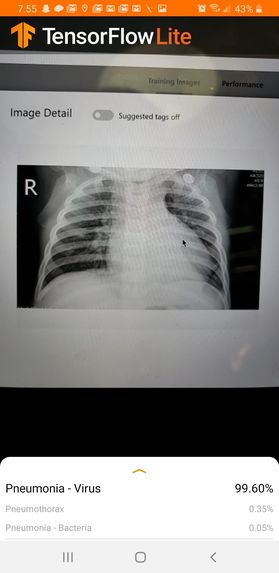

Bion is a Telemedicine Systems-Operation Platform for world-class physicians, high quality care, and user-friendly experiences which makes an Ideal Place for patients to get their primary care online. Bion uses Machine Learning Algorithms to diagnose different types of Pulmonary diseases through chest X-Rays.

Mobile Android App Development. TensorFlow Deployment using tfjs + tfLite